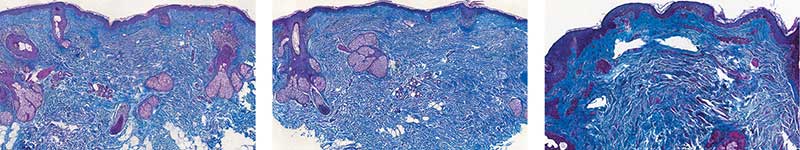

Рис. 2. Пациентка Л. Окраска по Ван-Гизону: A – до процедуры; B – через месяц после процедуры; C – через пять месяцев после процедуры